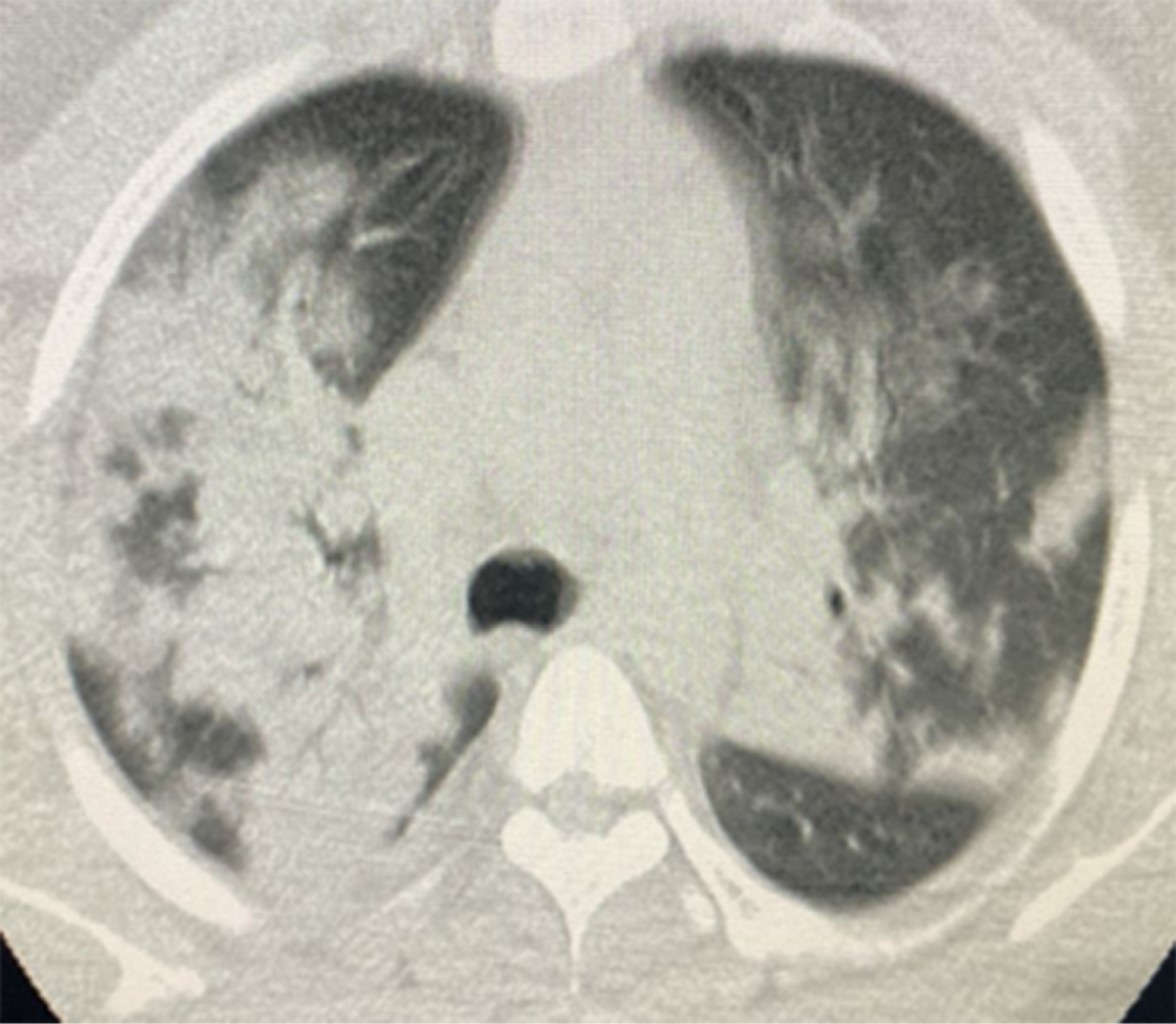

Figure 1